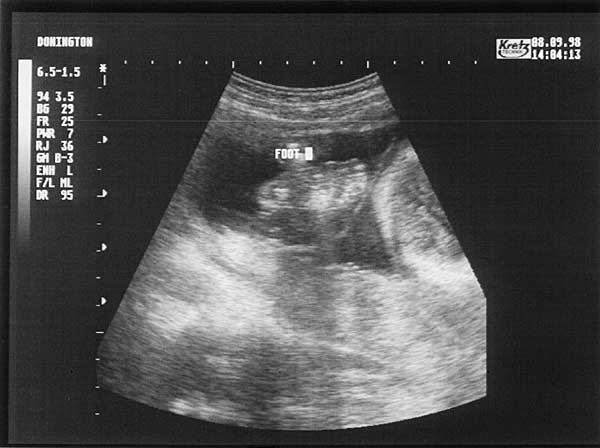

24 Weeks - Tuesday 8th September 1998.

Twenty Four Week Scan 1